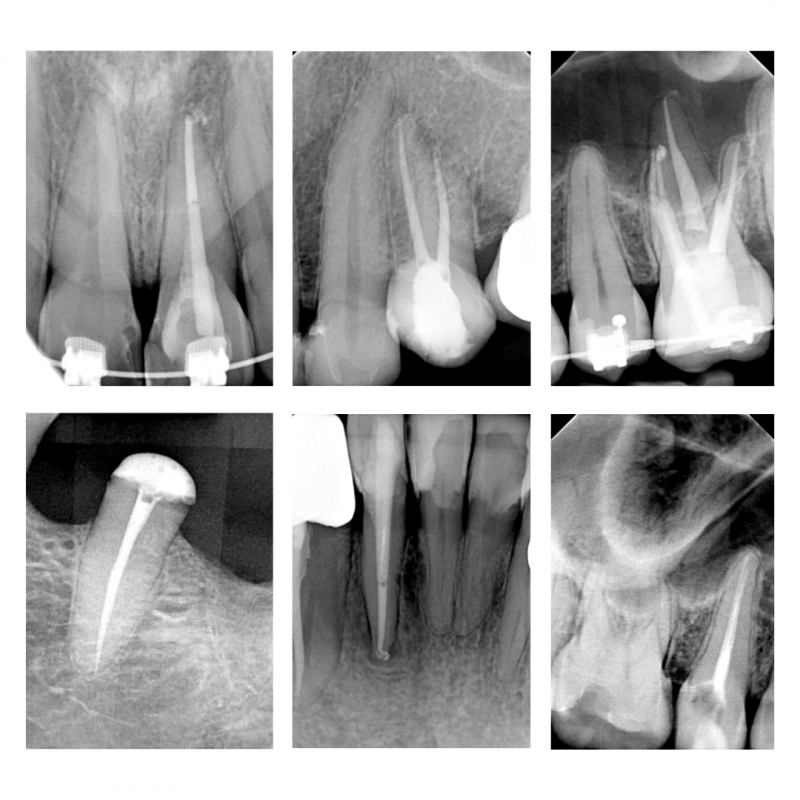

Stan przed i po leczeniu powtórnym kanałowym zęba. Dzięki wykorzystaniu mikroskopu stomatologicznego usunięto złamane narzędzie, udrożniono oraz wypełniono kanały korzeniowe zęba.

Stan po wypełnieniu ostatecznym kanałów korzeniowych poszczególnych zębów.